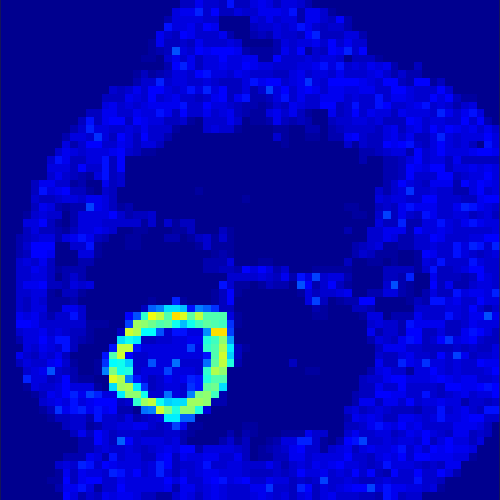

5.2 Monte Carlo Simulation

In order to test the behaviour of the proposed method in a more realistic, random-based test case, we performed a Monte Carlo simulation for dynamic SPECT imaging. First, we created a simple image phantom consisting of an outer and two inner circles which represents the structure of the region of interest (see figure 8(a)). Within those regions we assumed concentration curves over a time period of 90 time steps as displayed in figure 8(b). Based on the tracer intensity in an image frame at each time step, we created a variable number of random decay events (where the number is proportional to the average concentration in one pixel in the whole image frame per time step) with a probability proportional to the concentration in every subregion. They are detected by a virtual double head gamma camera rotating around the patient by 46 degrees per time step, which consists of 374 detector bins. Every simulated decay event is projected onto the scanner and counted by the corresponding detector bin.

In two different tests we fixed the number of events counted by the detector equal to (resp. ) times the average concentration in one pixel. The resulting sinogram images of the accumulated counts in each bin are shown in figure 9.

Based on the sinogram data we applied the proposed algorithm in order to reconstruct the original image sequence. The results for both test cases are shown in figure 10.

As one can see, the method is able to reconstruct the regions properly, even in case of a low count number. Within a number of iterations (average of 100 outer and 10000 inner iterations), the algorithm presents a reasonable reconstruction of the region of interest and the corresponding regional tracer concentration curves. Here, the parameters were not optimized as in the case of the synthesized data sets in the previous section, but kept fixed as , and . With futher optimized parameter values one could possibly provide even better results.